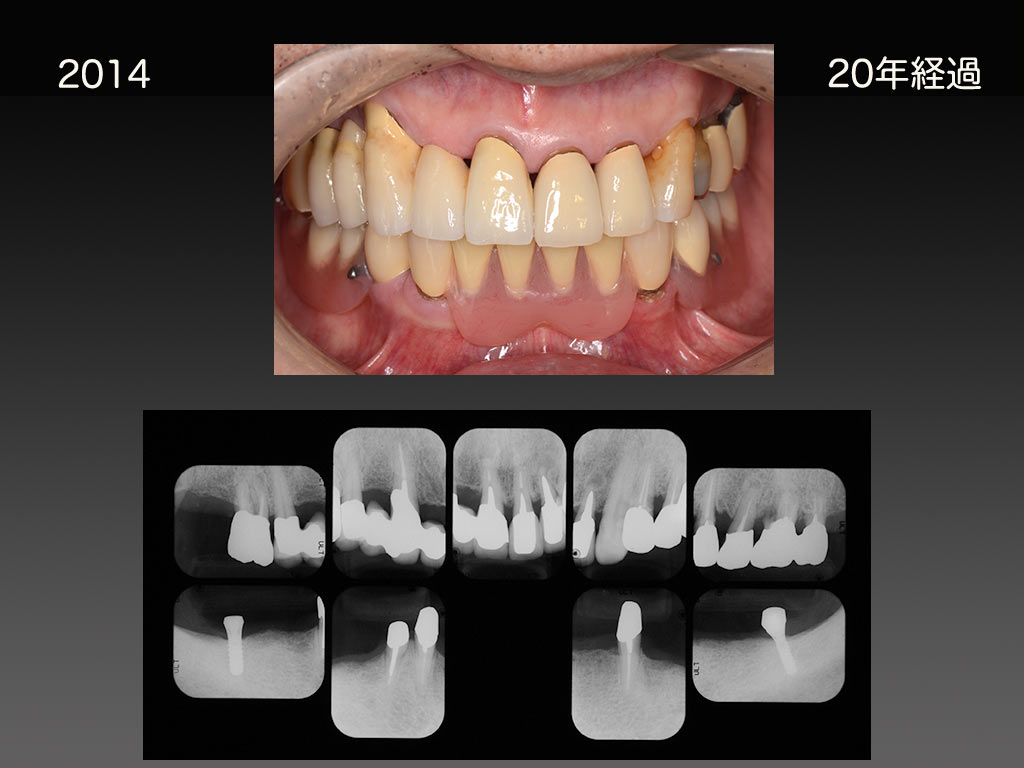

■治療例 2 20年以上使い続けている部分入れ歯

1994年に作製した部分入れ歯です。残っている歯は歯周病が進行していましたが、20年を越えました。わずか2本のインプラントの助けを借りることになりましたが、現在も新たな義歯を作製することなく使用していただいています。